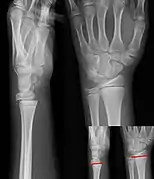

Additional images